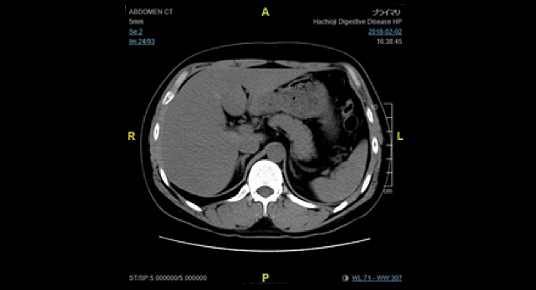

単純CT画像